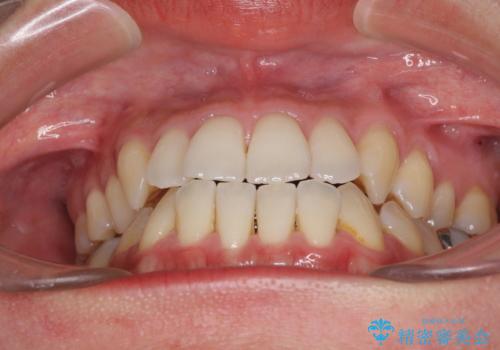

前歯のデコボコ インビザラインによる矯正治療

- 上下前歯の叢生と奥歯の反対咬合を気にして来院された患者様です。

インビザラインを用い、下顎はIPR(歯と歯の間を削る)と歯列全体を後方に移動させ、上顎は側方に拡大させることで歯列を改善していくこととしました。

骨格的に下顎が左側前方にずれているため、上下正中のズレや左右奥歯の咬み合わせを理想的な状態とすることは困難でした。